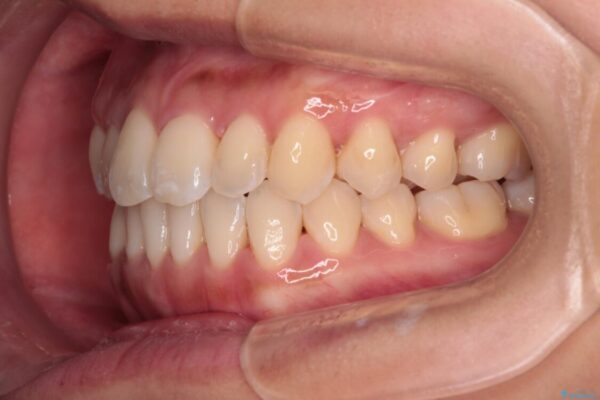

治療後

• 【モニター】前歯のデコボコをインビザラインで改善 治療後画像